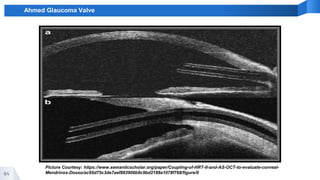

Ahmed Glaucoma Valve

Picture Courtesy: https://www.semanticscholar.org/paper/Coupling-of-HRT-II-and-AS-OCT-to-evaluate-corneal-

Mendrinos-Dosso/ac95d75c3de7aef883906b8c9bd2188a1078f768/figure/0